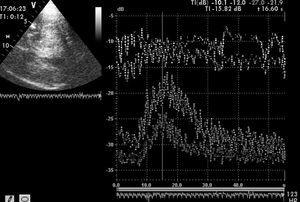

PARO CIRCULATORIO CEREBRALLa realización de la DTC como prueba precoz de ausencia de flujo cerebral en el diagnóstico del paro circulatorio cerebral, ante la presencia de sustancias depresoras del sistema nervioso central, permite disminuir el tiempo de diagnóstico de muerte cerebral69. Sin embargo, son conocidas las limitaciones del doppler ciego y las dificultades que a veces concurren en su realización e interpretación, siendo quizás el caso más claro la ausencia de señal acústica, que precisa para ser concluyente la existencia de una exploración previa. Ello ha motivado la búsqueda de ventanas de insonación alternativas en aquellos casos en que los estudios no sean concluyentes70.

Basándonos en la práctica adquirida durante 4 años podemos asegurar que muchas de estas dificultades se resuelven adecuadamente con el DTCC. Las marcas anatómicas de referencia en el estudio bidimensional nos indican dónde centrar la búsqueda. Además, la utilización del modo angio-DTCC es muy útil cuando la señal de color está ya muy debilitada por las bajas velocidades y los ecopotenciadores aumentan la localización de flujos de mínima intensidad3. Los patrones sonográficos utilizados son los mismos que en el DTC convencional71,72, pero su obtención resulta mucho mas sencilla. De esta manera, un artículo recientemente publicado ha demostrado una concordancia diagnóstica entre el DTCC y la angiografía cerebral del 100% en la confirmación del paro circulatorio cerebral73.